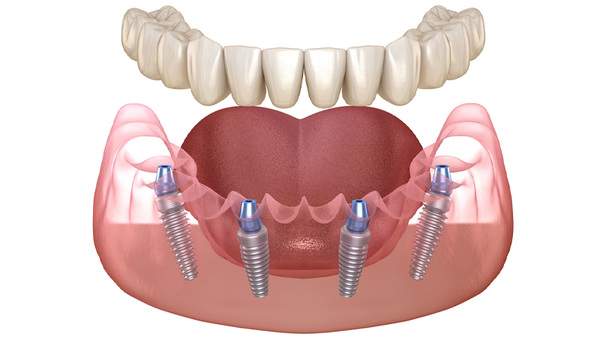

オールオン4(All-on-4)とは、片側だけもしくは上下の歯全てを失った方、又は抜歯予定の方のためのインプラント治療です。

最少4本〜6本のインプラントを埋入し、そのインプラントで総入れ歯の形をしたうわものを固定し、見た目と噛み合わせ機能を素早く回復させる治療法です。

全ての歯を失った場合、従来では8~14本のインプラントを埋入する必要があり、身体的・費用的負担の大きなものでした。

また、オールオン4は入れ歯を長年使って吸収してしまった顎の骨にも適応可能です。傾斜埋入という方法を用いることによって斜めにインプラントを打ち強固な固定を得ることができます。